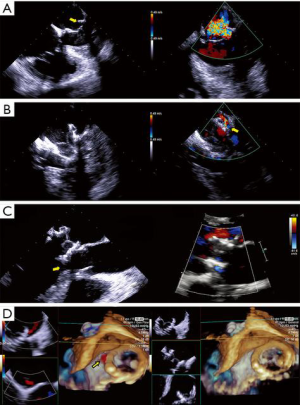

- Echocardiography, transthoracic (TTE) or transesophageal (TEE), is indispensable for diagnosis, procedure planning, intra-procedural guidance, monitoring complications and for patient follow-up. It is the imaging modality with the highest temporal resolution, adequate spatial resolution and the only one that can provide complete hemodynamic data. Several comprehensive reviews detail imaging protocols dedicated to mitral valve, as well as patient selection criteria for mitral procedures (3-5). Echocardiography can easily distinguish between degenerative and functional mitral regurgitation (DMR and FMR, respectively). DMR is a disease of the valve, which undergoes myxomatous degeneration, affecting the morphology and function of various structures: leaflet thickening, redundancy, prolapse and disjunction, or chordal rupture with a flail leaflet (Figure 2, Video 1) (6). DMR associates severe annulus dilatation, with a highly eccentric regurgitant jet that peaks at end systole and is oriented away from the diseased leaflet. In contrast, FMR is a disease of the ventricle, where a tethered or apically displaced papillary muscle impairs the closure of an otherwise morphologically normal valve, followed by annular dilatation. The FMR regurgitant jet peaks in early systole, is less eccentric and is oriented toward the culprit leaflet. Arguably, the severity criteria for FMR versus DMR may be different (5,7). The regurgitant jet volume is influenced by intravascular volume and left ventricular afterload. This explains the significant changes in MR severity assessment between interval examinations. TEE tends to overestimate MR severity, compared to TTE, if only a semiquantitative assessment of color Doppler is used. MR evaluation should be performed only during euvolemic state, keeping the recommended Nyquist limits for color Doppler (50–60 cm/sec) and proximal isovelocity surface area (PISA) measurements. Quantitative methods may overestimate highly eccentric or non-holosystolic jets. Gross errors commonly result from analysis of single frame color Doppler images, ignoring the dynamic changes of the regurgitant orifice area and jet volume. Lastly, the angiographic classification of MR severity does not overlap the echocardiographic severity grading. As none of the echocardiographic techniques fully characterizes MR, the proper evaluation of this condition requires considerable skill and experience. Mitral stenosis (MS) severity is largely based on valve area, with a threshold of 1.5 cm2, as transmitral gradients are highly variable and related to the heart rate and transmitral flow. While such a simplification is appealing, relying on valve area only may lead to inappropriate clinical decisions. Area measurement is prone to technical errors, using only planimetry of 2D cross sectional views, 3D ventricular views of leaflet edges, or 3D atrial views of the funnel shaped, calcified valve, where clearly defined measurement points are lacking. It is important to understand the difference between the geometric valve area resulting from planimetry and the smaller effective area of Doppler based methods: pressure half-time and continuity equation. In patients with symptoms out of proportion to TTE findings, supine bicycle exercise echocardiography reveals increased, exercise-induced mitral gradients and pulmonary systolic pressure, correlated with stress induced symptoms, even in the presence of a valve area >1.5 cm2 (8). Definition of device success in mitral procedures relies on criteria published by the Mitral Valve Academic Research Consortium (MVARC): reduction of MR to < moderate, transmitral gradient <5 mmHg, effective valve area >1.5 cm2, and LVOT gradient <20 mmHg (9). These parameters are measured 30 days post-procedure to allow for left atrial remodeling and functional recovery. One must again remember the difference between geometric and effective areas, which is more pronounced for the slit-like orifice of mitral stenosis, compared to the more rounded orifice of a TMVR device.

- Edge to edge repair. MitraClip® technology replicates the Alfieri edge-to-edge stitch repair of MR and is exclusively driven by echocardiography (Figure 9, Video 3). It has been used in >50,000 patients, with FDA approval limited to DMR as a class IIb indication in patients with prohibitive surgical risk. It achieves MR reduction and may preclude surgical repair in failed cases (5). The echocardiographic patient selection criteria and the intraprocedural guidance principles have been extensively described (5,27,28). Experienced operators commonly obtain patient, procedural and technical success, with acceptable device success, as defined by MVARC (9). The long-term hemodynamic impact of MitraClip® implantation has been less enthusiastically studied. Echocardiography-based mitral valve sizing and regurgitation quantification relies on several assumptions: single, static, rounded regurgitant orifice and single, central, non-eccentric, holosystolic jet, without associated MS. Post-clip deployment, these assumptions are violated, as a double orifice is created, frequently accompanied by two regurgitant jets. Area measurement of the double orifice is limited to the planimetry of cross-sectional views. A definition of MS post MitraClip® patients does not exist; a pressure halftime of >91 m/sec was found to correlate with high post-procedural gradients. Post-procedural mitral gradients are difficult to predict. Typically, they are mildly elevated compared to baseline and tend to not increase proportional to the number of clips implanted, even at higher heart rates, but raise significantly with exercise echocardiography. The residual regurgitation evaluation is limited to semi-quantitative color Doppler data, as PISA method is not validated for double orifices and jets. The impact of a persistent interatrial defect and shunt is not well understood and closure is advocated in patients with pulmonary hypertension and failing right ventricles. Notably, recent data shows absence of post implant LV remodeling in patients with LVEF <40%, in contrast with earlier reports (29). Imaging MitraClip® patients remains largely operator-dependent requires development of specific criteria to clearly define device success and complications.